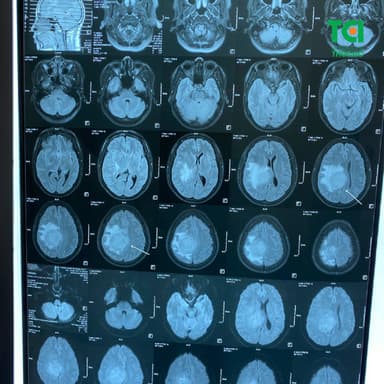

2.2. Chẩn đoán hình ảnh u màng não bằng kỹ thuật chụp cộng hưởng từ

Là phương pháp chẩn đoán chính xác và cho hình ảnh rõ nét nhất về vị trí, kích thước và mức độ xâm lấn của khối u. Trên phim MRI, u màng não thường xuất hiện dưới dạng khối bám vào màng cứng với chân rộng, được ngăn cách với nhu mô não bởi một viền đen mỏng đặc trưng. MRI còn giúp đánh giá tình trạng phù não quanh u và mối liên hệ của khối u với các cấu trúc quan trọng xung quanh như mạch máu, thần kinh và nhu mô não.